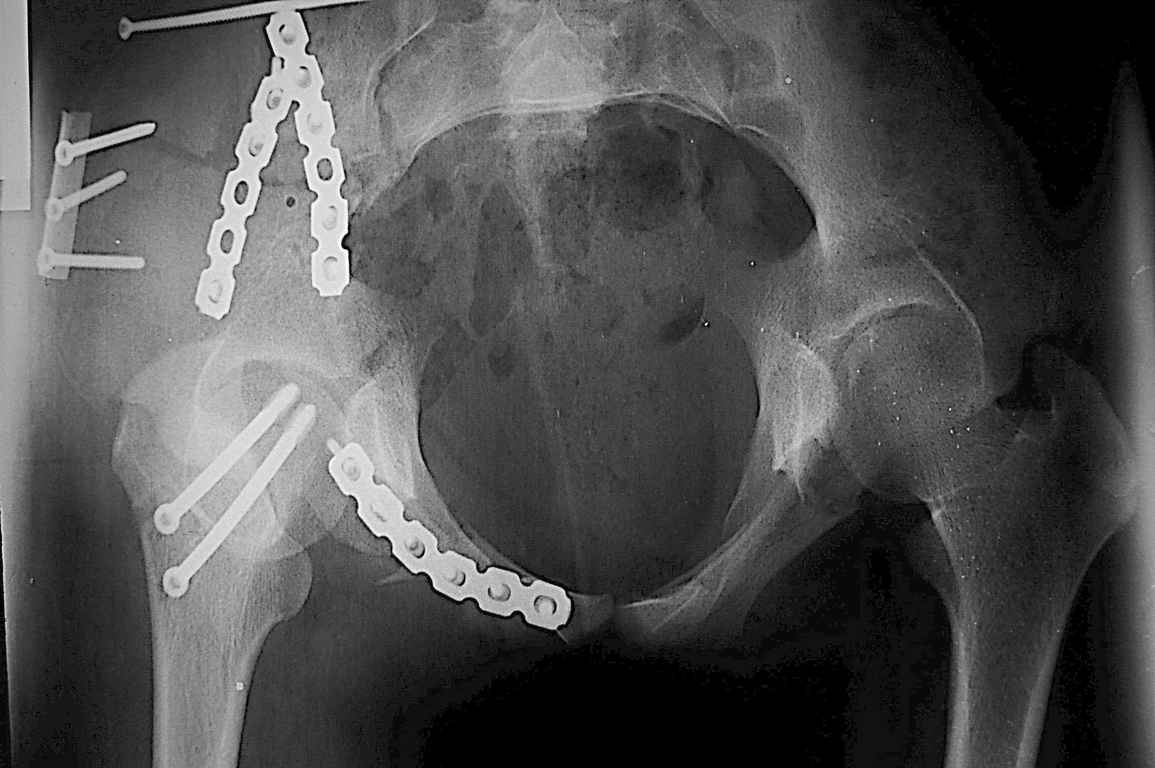

Уважаемый Алексей, на представленных Вами снимках имеется вертикально-нестабильное повреждение тазового кольца без повреждения вертлужной впадины. Учитывая это, а так же растущий возраст ребенка я бы выбрал аппарат внешней фиксации в виде кольцевой опоры, т.к. не смотря на оскольчатый перелом крыла в переднем отделе можно ввести минимум 2 стержня + 1-2 надвертлужно. Этого будет достаточно чтобы "зацепится", выполнить репозицию и дальнейшую фиксацию. Перелом шейки по моему лучше прооперировать 3 канюлированными винтами по АО.

Шейку срочно закрыто винтами.

Таз - подвздошным и падлобковым доступом раздельные рекострукционные пластины 4 штуки. Сплошную пластину как у взрослых нельзя (из-за роста придется доставать)

1 аппаратом сложно управлять при оскольчатом переломе крыла

2 для будущей мамы желателен максимально восстановленный таз